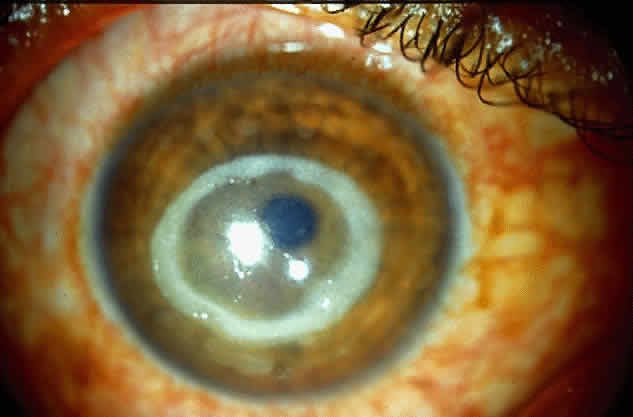

Acanthamoeba infection of the cornea is being reported with increasing frequency. While this is associated with contact lens wear in industrialized countries, in developing countries it is almost exclusively seen in non-contact lens wearers (Fig. 4).6 Misdiagnosis and inappropriate treatment are common.

|